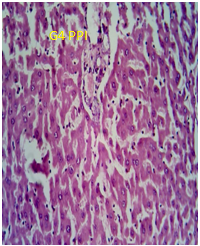

The error in the image in fig. 9 in the published research article has occurred from our side due to the magnification variation and oversight while placing the same in our article which was submitted for publication in your reputed journal. The error is unintentional and due to multiple experiments compilation for the said promising research.

“The image of “G5 PPI group” in fig. 9 is incorrect in the original figure. A corrected fig. is shown below.”

Liver

Fig. 9: Photomicrograph of sections of brain and liver of animals of control group and animals administered with a single dose of 250 mg/kg to PEGylated G4 and G5 PPI dendrimers after 24 h. (magnification: 400X)